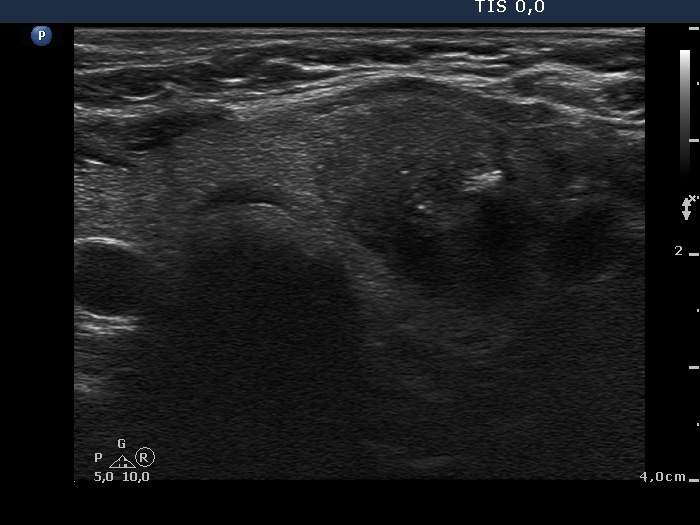

Medullary carcinoma (histological diagnosis) - case 638

There is an irregular minimally hypoechogenic-echonormal small patch in the central part of the hypoechogenic nodule. This figure has one bright granule in the left image.